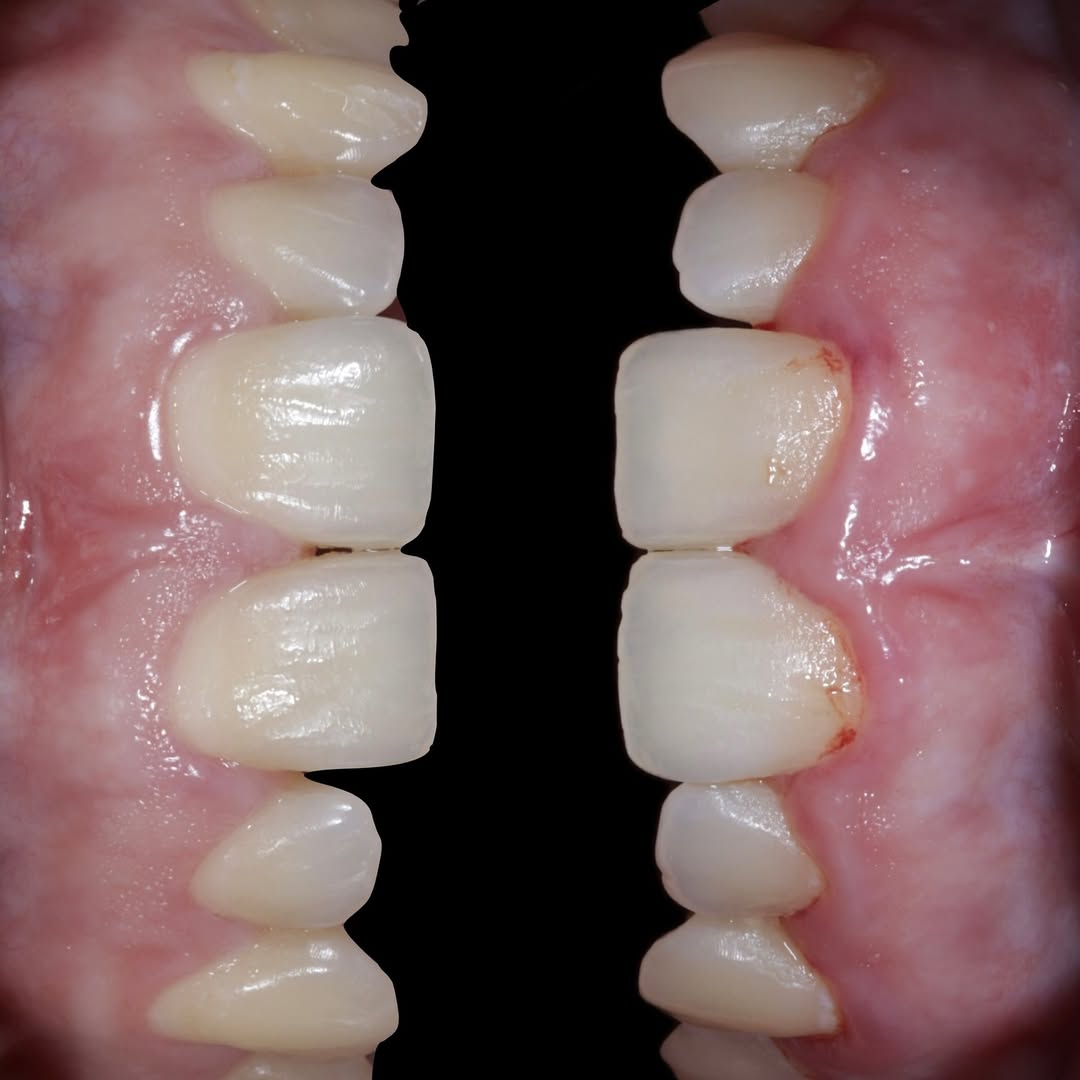

Aprende la planificación y técnica de la cirugía Mucogingival para el recubrimiento de recesiones y aumento de banda queratinizada en el sector anteroinferior

Durante una mañana, asistirás a una Cirugía Mucogingival de recubrimiento radicular de recesiones múltiples en IV y V sextante (36 a 43).

Gracias al uso del microscopio y a la proyección en tiempo real en pantalla, verás exactamente lo mismo que veo yo durante la cirugía, sin tener que estar